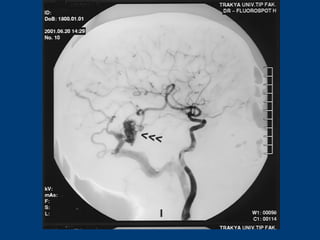

 İ.A.: 27 yaşında erkek hastaİ.A.: 27 yaşında erkek hasta

 BaşağrısıBaşağrısı

CERRAHİCERRAHİ

 Sol oksipital kranyotomiSol oksipital kranyotomi

 AVM’nin total rezeksiyonuAVM’nin total rezeksiyonu

 PostoperatifPostoperatif

Nörolojik Muayene ve DSA:Nörolojik Muayene ve DSA:

NormalNormal